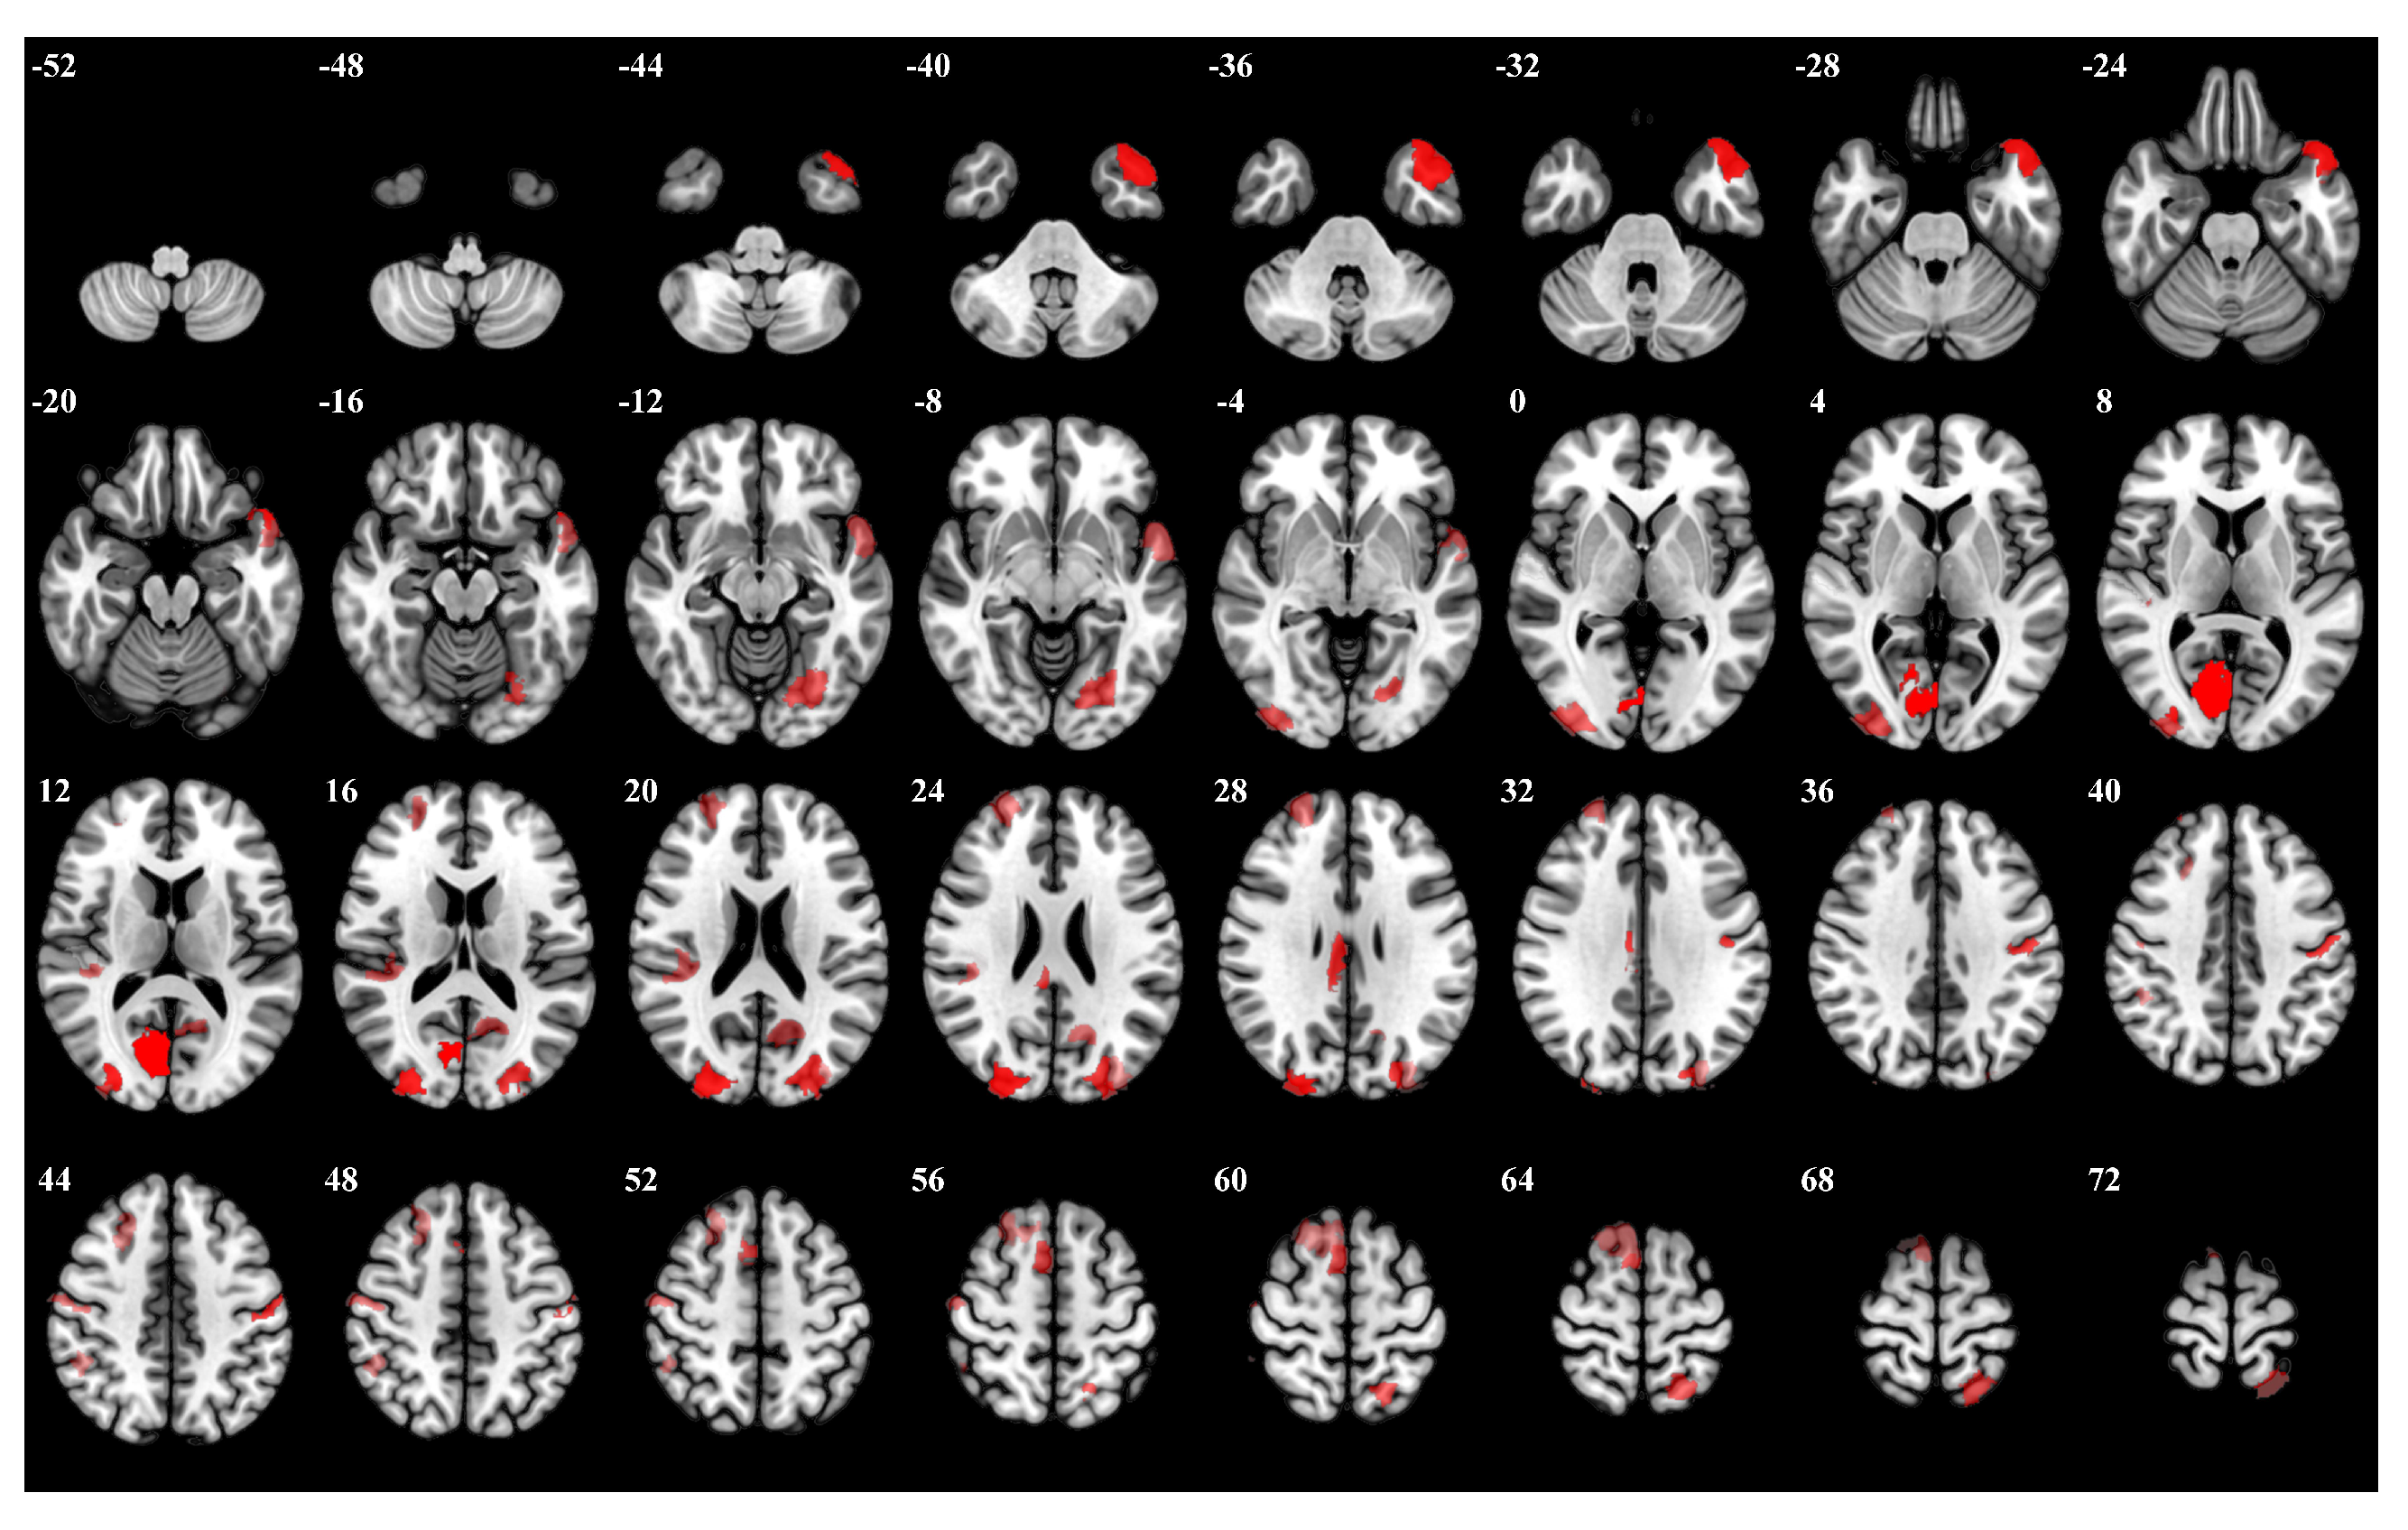

In the 0-back task, participants were instructed to respond to a specific target number stimulus. The right hemisphere visual cortex, particularly regions Right Hemisphere Visual 19 and Right Hemisphere Visual 26, exhibited high importance weights. Moreover, left hemisphere regions such as Left Hemisphere Limbic Temporal Pole 6 and Left Hemisphere Visual 27 were also significantly activated. The left hemisphere somatosensory-motor cortex, Left Hemisphere Somatomotor 17, showed notable activity. Figure 5 presents a visualization of the top 5 percent of the most influential ROIs during the 0-back task, accompanied by Table A1, which outlines the details of the brain regions.

Figure 5.

The top 5 percent of the most influential ROIs for 0-back, with higher opacity indicating higher influence weights.

In the 2-back task, participants had to respond whenever the current stimulus matched the one presented two stimuli back. The right hemisphere dorsal attention network exhibited substantial activation, particularly regions Right Hemisphere Dorsal Attention Posterior 15 and Right Hemisphere Dorsal Attention Posterior 9. Moreover, the bilateral visual cortex regions Left Hemisphere Visual 25 and Right Hemisphere Visual 29 showed significant activation. Figure 7 and Table A3 provide the details for the 2-back task, as above.

Figure 7.

The top 5 percent of the most influential ROIs for 2-back, with higher opacity indicating higher influence weights.